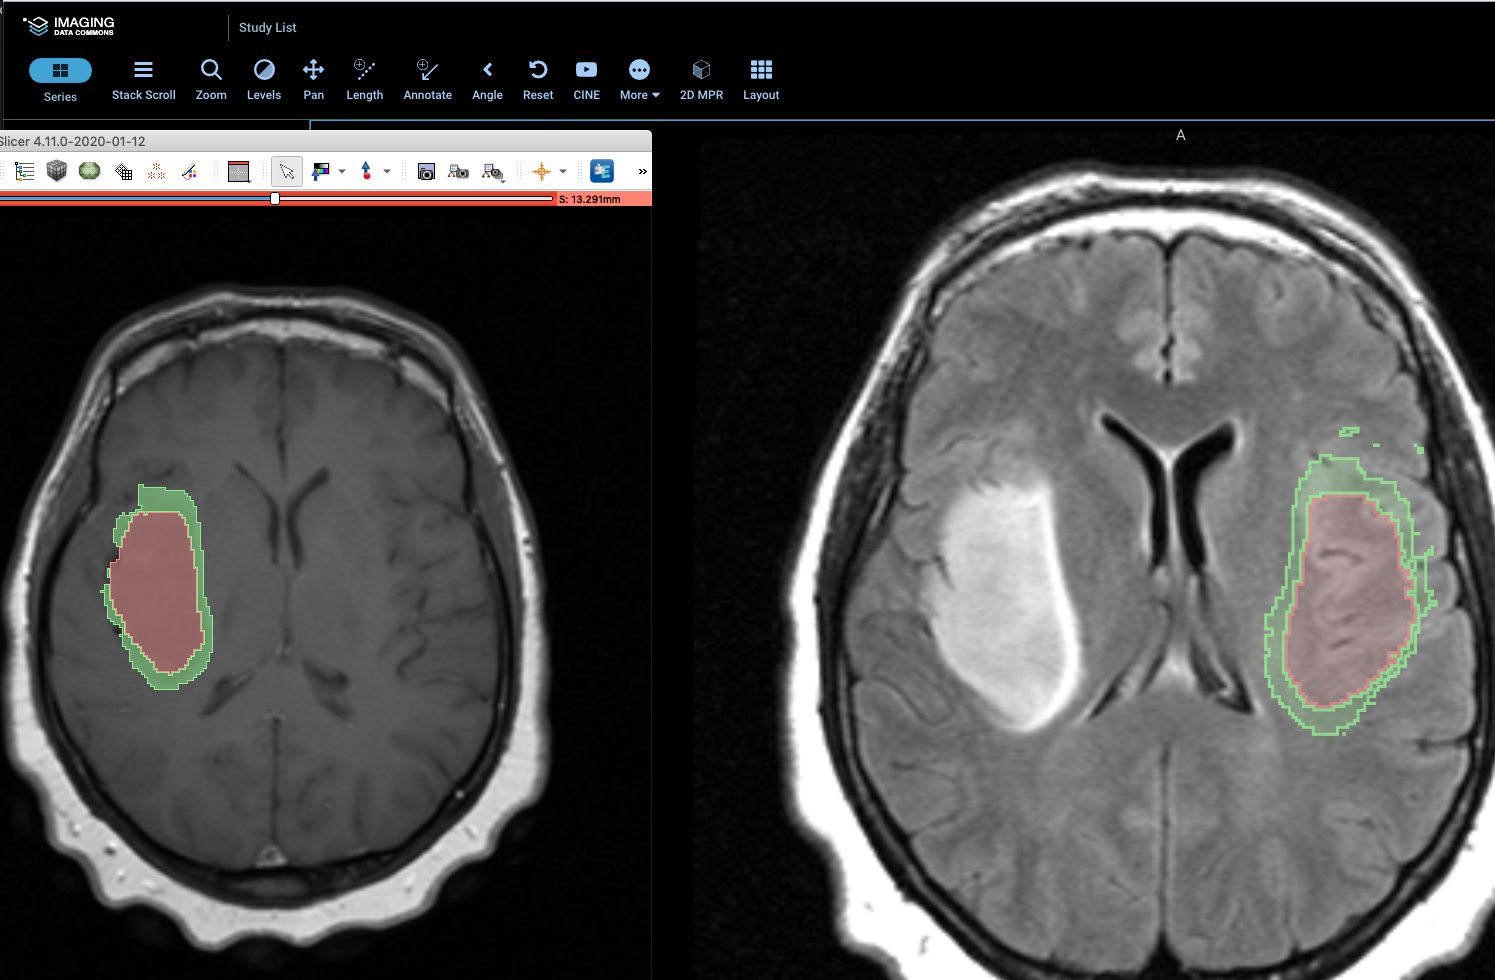

We have an inconsistency in displaying segmentation for T1 for this study (and for all segmentations in LGG/GBM collections) between Slicer and OHIF.

Notably, orientation of the SEG is different than MR for all those cases. It was observed that overlay is wrong in MPR as well.